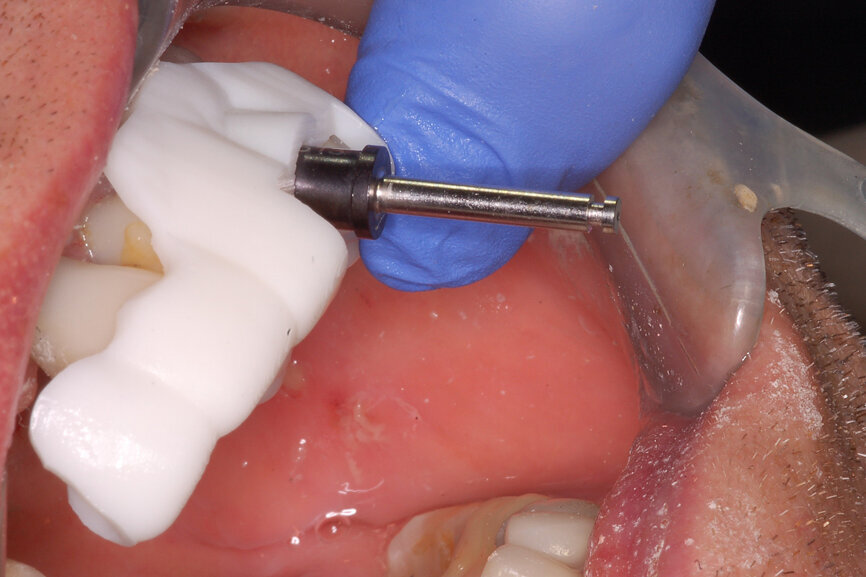

Fig. 17a: Utilising the tooth-borne template and the first insert, initial long shaper drills were used to reach the apex of the root.

Fig. 17b: Utilising the tooth-borne template and the first insert, initial long shaper drills were used to reach the apex of the root.

Prior to the guided drilling, a Gates–Glidden drill was used to remove any gutta-percha within the root. Utilising the tooth-borne template and the first insert, initial long shaper drills (IS1, IS2) were used to reach the apex of the root (Root Membrane Kit; Fig. 17). A periapical radiograph confirmed that the apex length had been reached and that all the gutta-percha had been removed (Fig. 18). The second insert had a metal cylinder that allowed for the long, round diamond drills to shape the root into the desired crescent shape (Fig. 19a). The insert was removed to access the palatal root (Fig. 19b). Using appropriate instrumentation such as periotomes, elvatomes or FRINGS forceps (both TBS Dental), the palatal root was carefully removed (Fig. 20). A periapical radiograph confirmed that the palatal root had been completely removed (Fig. 21). The next insert contained the final diameter to receive the guided sleeveless drills for osteotomy preparation (Fig. 22a). The osteotomy was prepared to avoid proximity to the remaining root fragment while leaving sufficient restorative space, as previously planned in the software simulation (Fig. 22b). Implant placement (AnyRidge, MegaGen) was facilitated by the R2GATE surgical carrier for full-template guidance at the appropriate torque values (Fig. 23). Depth control and rotational positioning were accurately confirmed with the notch indicated on the template to correspond with the insertion tool (Fig. 24).